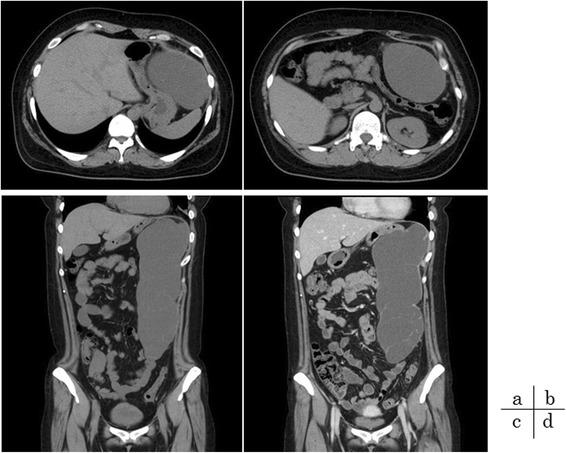

We report a rare case of huge amebic intra-abdominal tumor with asymptomatic amebic colitis. This appears to represent the first report of amebic intra-abdominal tumor. A 31-year-old woman presented to a local doctor with only a sensation of abdominal fullness. Abdominal computed tomography (CT) showed a huge intra-abdominal tumor in the left abdominal cavity, and she was referred to our hospital. Colonofiberscopy for detailed examination showed multiple slight, discrete ulcers in the cecum. Ameboid trophozoites were identified from biopsy specimens, and asymptomatic amebic colitis was diagnosed. Oral metronidazole (MTZ) was administered at 1500 mg/day for 10 days. CT 14 days after starting MTZ showed no change in the intra-abdominal tumor, and resection of the tumor was therefore performed. Pathological examination revealed Entamoeba histolytica with engulfed erythrocytes complicated by hemorrhagic cyst. If an intra-abdominal tumor is present and colitis is observed, amebic intra-abdominal tumor should be considered among the differential diagnoses.

我们报告了一例罕见的巨大阿米巴性腹腔内肿瘤合并无症状阿米巴结肠炎的病例。这似乎是阿米巴性腹腔内肿瘤的首例报告。一名31岁女性因仅有腹部饱胀感就诊于当地医生。腹部计算机断层扫描(CT)显示左腹腔有一个巨大的腹腔内肿瘤,随后她被转诊至我院。为进行详细检查而做的结肠镜检查显示盲肠有多个轻微、散在的溃疡。从活检标本中鉴定出阿米巴滋养体,诊断为无症状阿米巴结肠炎。给予口服甲硝唑(MTZ),剂量为1500mg/天,共10天。开始使用MTZ 14天后的CT显示腹腔内肿瘤无变化,因此进行了肿瘤切除术。病理检查显示溶组织内阿米巴伴有吞噬红细胞,并伴有出血性囊肿。如果存在腹腔内肿瘤且观察到结肠炎,在鉴别诊断中应考虑阿米巴性腹腔内肿瘤。